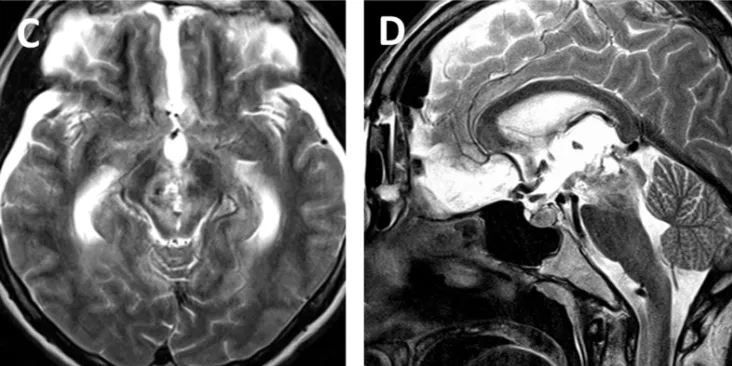

术后MRI显示轴内血肿及血管病变已完全切除(图c, d)。